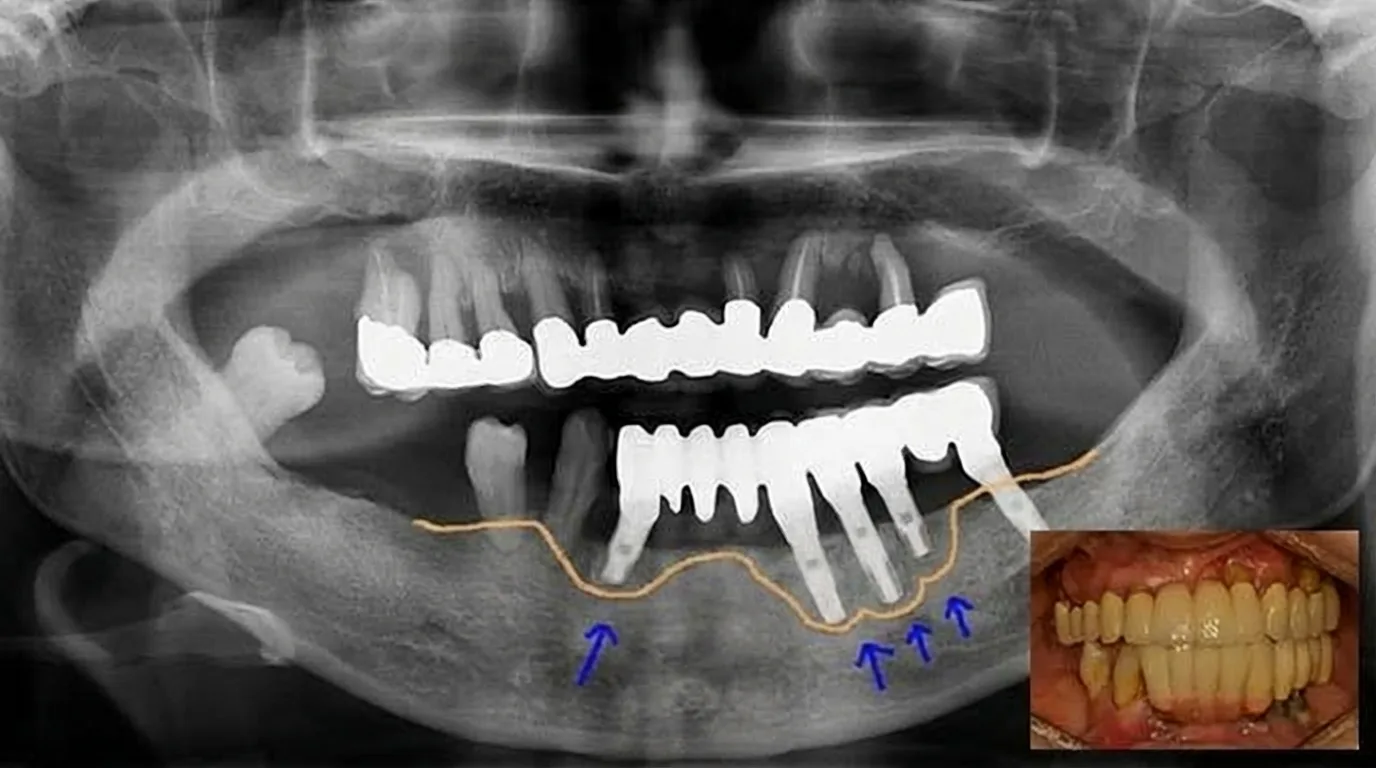

-과거에 부정확한 위치에 식립된 경우 저작 시 통증, 음식 끼임, 심미적 불편이 발생

-오랜 사용 후 뼈가 소실되어 다시 치료가 필요한 경우

임플란트가 실패한 부위는 뼈가 약해져 있거나 염증 흔적이 남아있는 경우가 많습니다. 따라서 재수술은 단순히 다시 심는 것이 아니라 원인을 정확히 찾고, 구조를 회복시키며, 다시 안정적인 상태로 만드는 과정이어야 합니다.